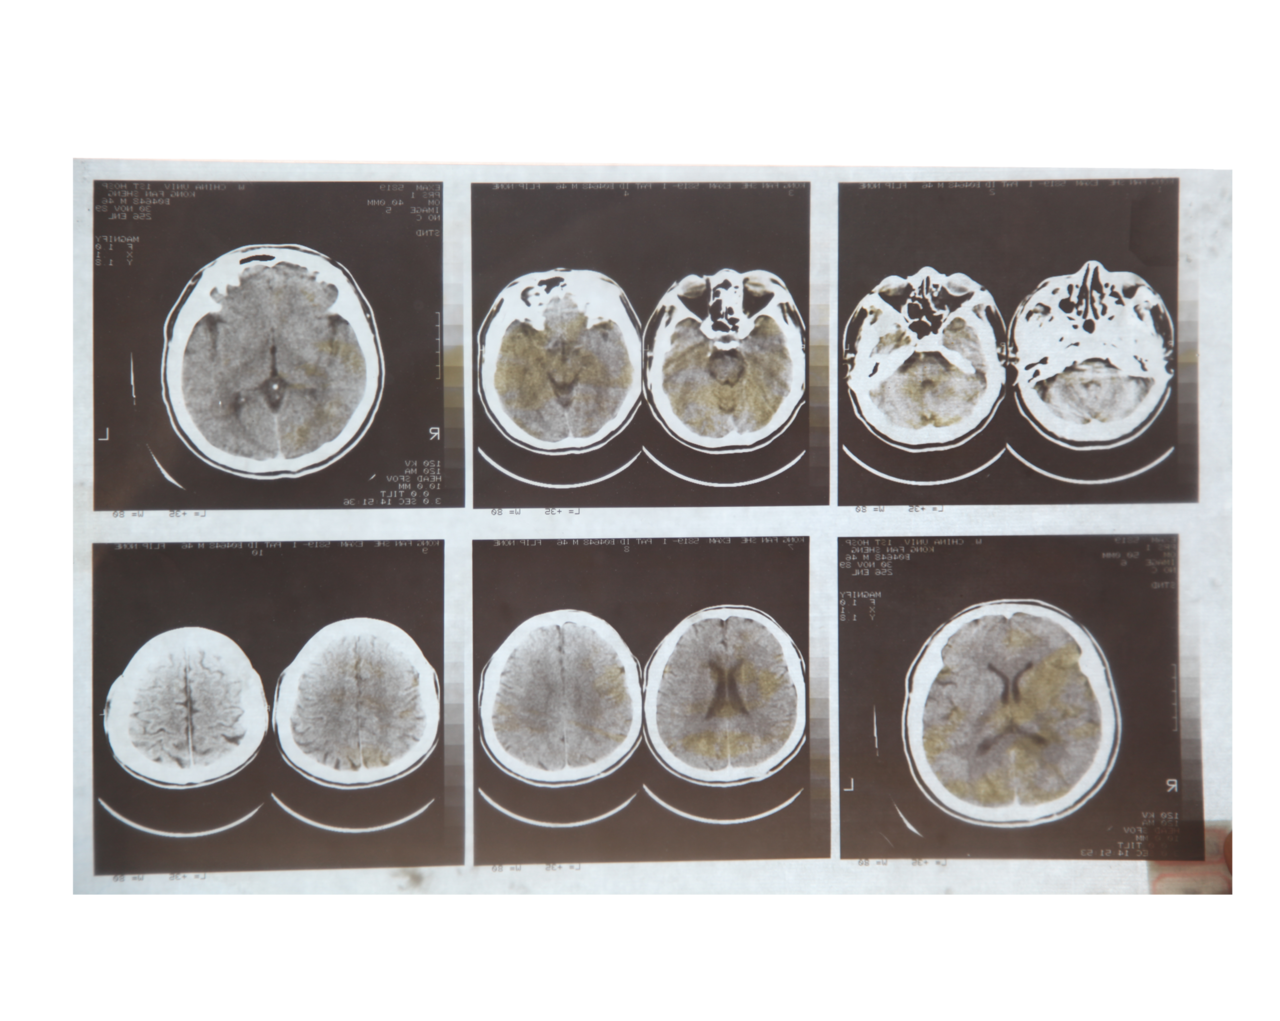

脑ct报告单图片,脑ct诊断报告单图片

孔繁森出车祸的脑ct片

朱欣月的脑部ct图像.点击此处查看全部新闻图片朱欣月的脑部ct图像.

脑ct诊断报告单图片

脑ct报告单图片头颅

脑ct片子图片

脑ct图片讲解

脑部ct图片真实

脑ct图片讲解正常

脑出血ct图片